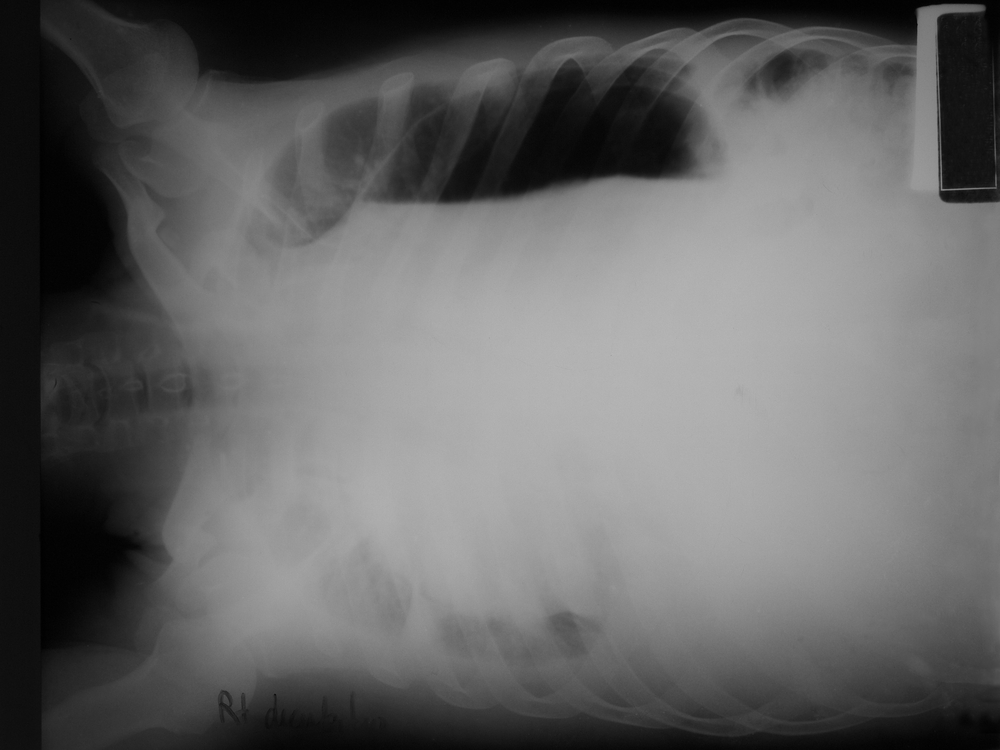

- рентгенографию грудной клетки;

Наиболее информативным методом диагностики при этой патологии является Эхо-КГ. Во время его проведения врач определяет размер расхождения (сепарации) между париетальным и висцеральным листками перикарда. В норме оно не должно превышать 5 мм. По этому параметру врач может сделать выводы о стадии гидроперикарда:

- начальная – 6-10 мм;

- умеренная – 10-20 мм;

- выраженная – более 20 мм.

Также проводится количественная оценка объема транссудата:

- незначительный – до 100 мл;

- умеренный – до 500 мл;

- большой – более 500 мл.

При сепарации листков перикарда более 20 мм больному обязательно проводится пункция перикарда под контролем Эхо-КГ или рентгенографии. В транссудате обнаруживаются признаки его отличия от экссудата: